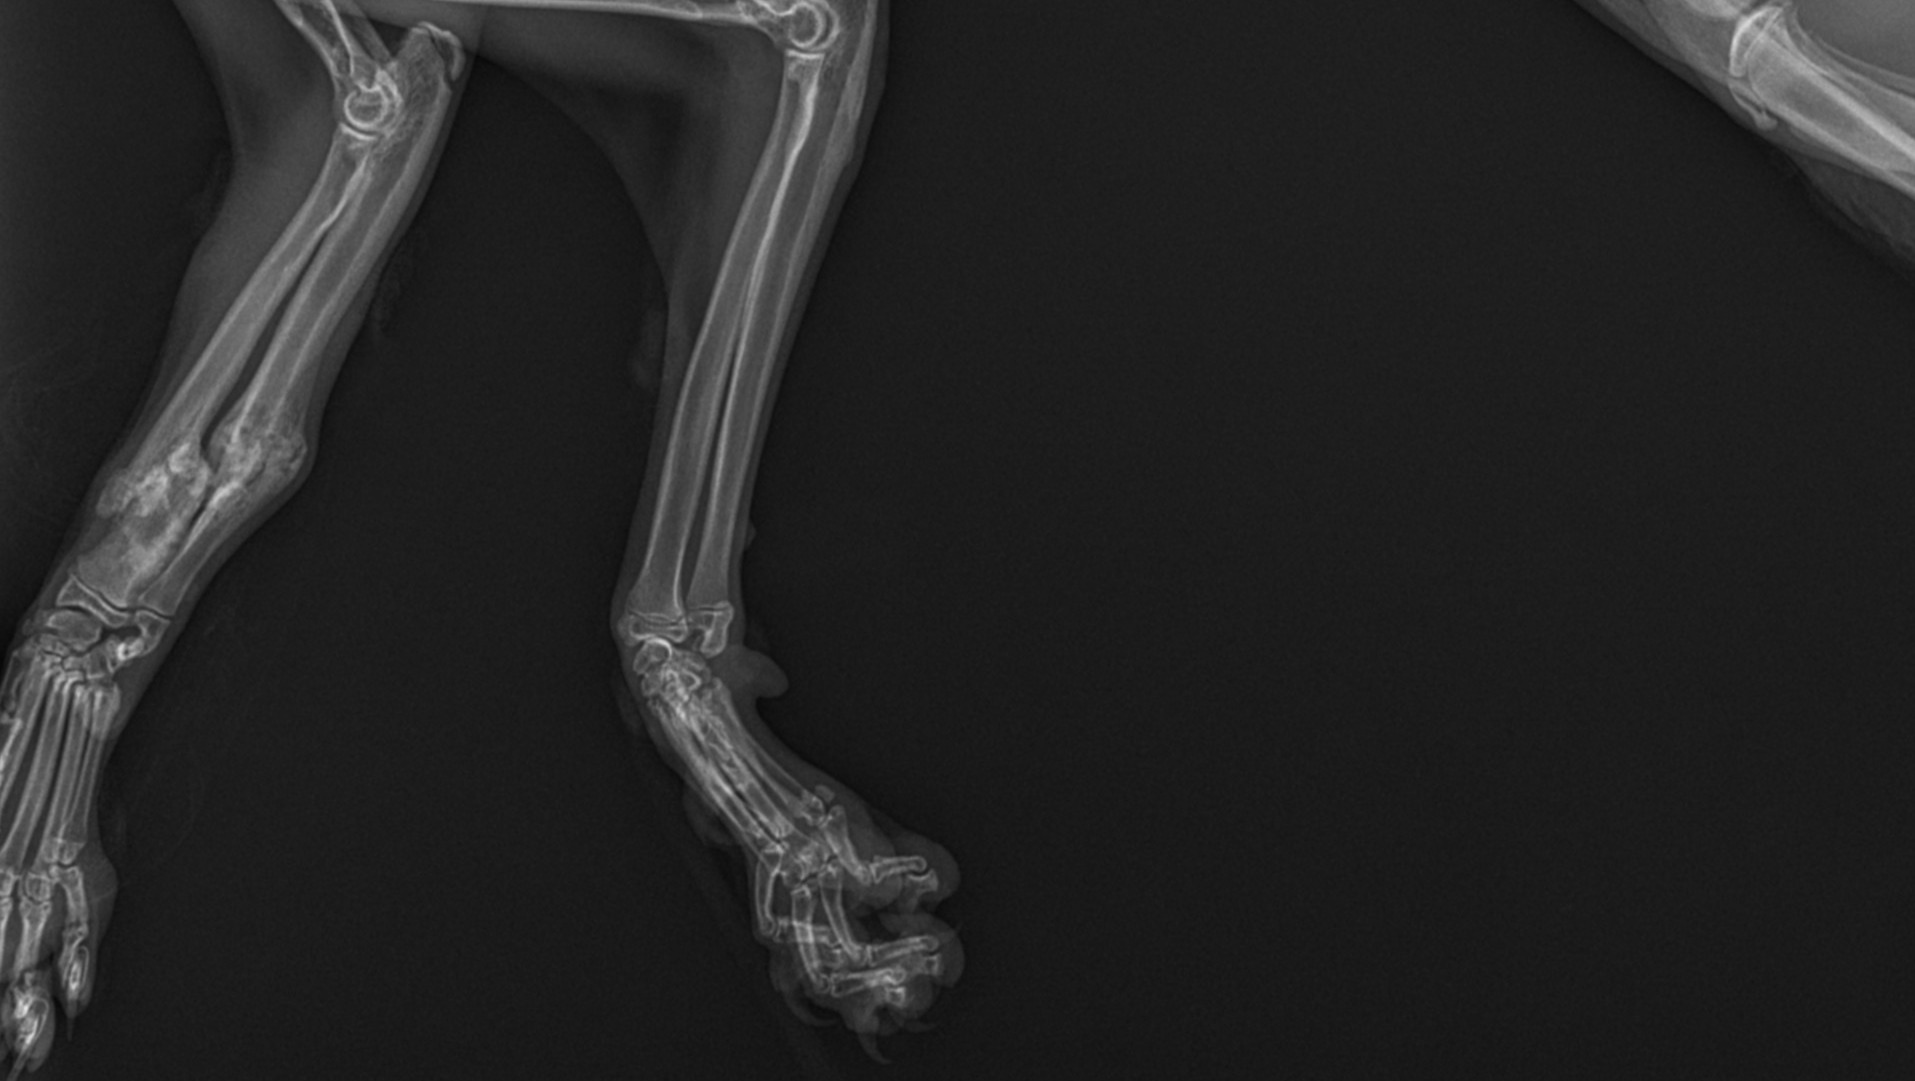

We rushed her immediately to an emergency veterinary clinic, where she weighed 3.9 lbs., about half what an eight-month-old kitten should weigh. The exam found multiple wounds from head to tail, her left leg was extremely atrophied and paralyzed with likely radial nerve damage, her left elbow was raw from pulling herself along with it, and her left wrist was also injured. X-rays showed the biggest surprise though... her "good" leg, the right front, had broken radius and ulna bones (a compound oblique fracture) from about 6 weeks prior, which had rotated 60 degrees and is healing out of alignment. It was clear that Annie had suffered traumatic injuries consistent with being hit by a car, and it happened within days of escaping more than six weeks prior.

This explained why her left elbow was scraped raw, and why she was so skinny: for six weeks her right front leg was broken and her left front leg was basically paralyzed from the elbow down, so the only way that this poor kitten could move around to find food was to drag herself using her left elbow. We have no idea how Annie was able to find food or even protect herself from feral cats and any other threats with no working front legs for six weeks. A few days later the labs came back that she also had the Giardia parasite, probably exposed at the same time as Apollo before she escaped, and she also had Hookworm.

The orthopedic veterinary surgeon is confident that once the right leg has healed completely, he can re-break the radius and ulna, realign everything properly, and reinforce it with a metal plate so she can walk normally on it. If we don’t do the surgery, he believes Annie would develop severe arthritis and other joint issues. This surgery is estimated at $6,000 to $10,000, on top of the $3,000 already paid. The prognosis for the left front leg is not as good, with amputation as the most likely outcome.

Not wanting to rush into an amputation, we began physical therapy and are trying to see what is wrong with her left front wrist in the hopes that once we fix the wrist she might be able to use the left leg again. If surgery on the wrist is needed it will likely cost about the same as the right leg surgery, plus the cost of physical therapy before and afterwards, etc. If the left wrist cannot be corrected, then the entire left leg will probably have to be amputated at the shoulder in order to prevent her from trying to chew it off (animals will often try to do this when they have a damaged limb).